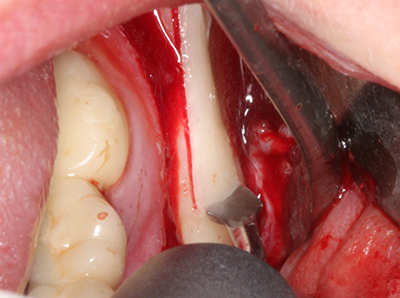

Fig. 3: Basal separation of the block is easier with specially angled attachments.

Fig. 13: Adequate irrigation with the 4-mm residual bone width is essential for this 52-year-old patient during the bone splitting.

Fig. 22: The mobile segment can be precisely separated with the thin osteotomy saw (W&H Piezomed).